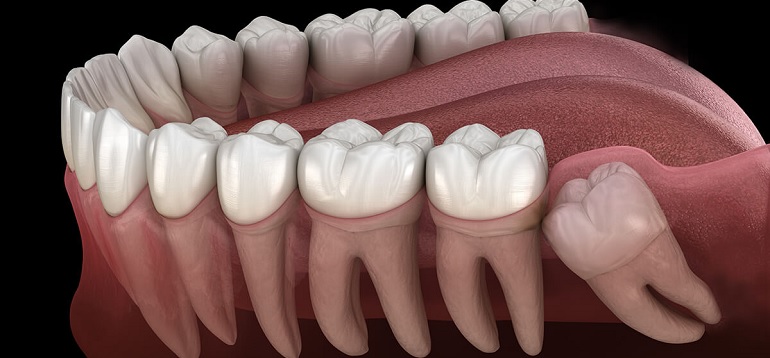

wisdom teeth often erupt partially or completely impacted,

Read MoreWisdom Tooth ? Causes, Symptoms, and Effective Solutions (2025)

Wisdom teeth, those pesky molars at the back of your mouth, can sometimes cause

If you’ve ever experienced the excruciating pain of an impacted wisdom tooth

wisdom teeth often erupt partially or completely impacted,

Read MoreWisdom Tooth Extraction: A Guide to Understanding Removal, Recovery, and Aftercare

Discover everything you need to know about wisdom tooth extraction.

Read MoreWisdom Teeth Removal - When, Why & How

Explore our comprehensive guide on wisdom teeth removal.